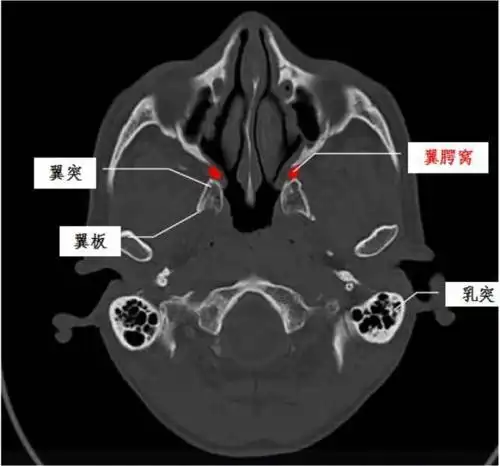

蝶骨: 体(蝶窦): 蝶鞍,垂体窝 小翼:视神经管,眶上裂 大翼:圆孔,卵

翼腭窝的ct影像解剖